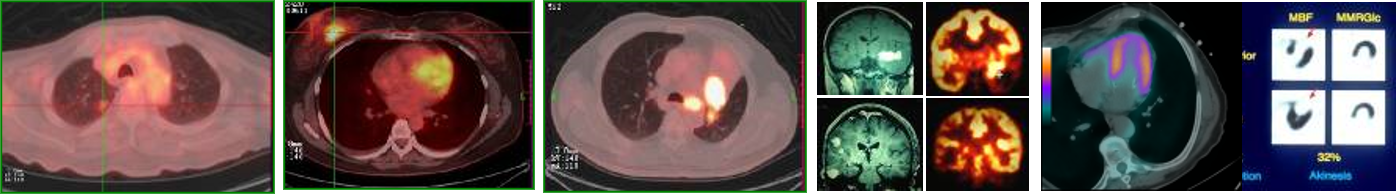

功能成像专题

功能成像的方式和特点;